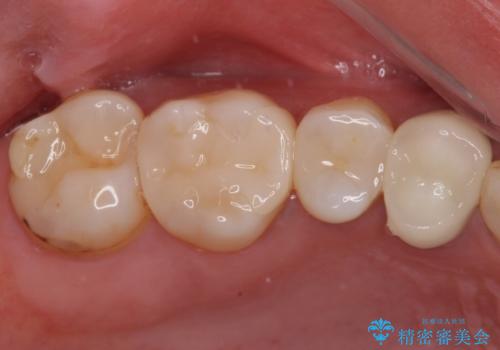

欠けてしまった奥歯 セラミッククラウンとセラミックインレーによるむし歯治療